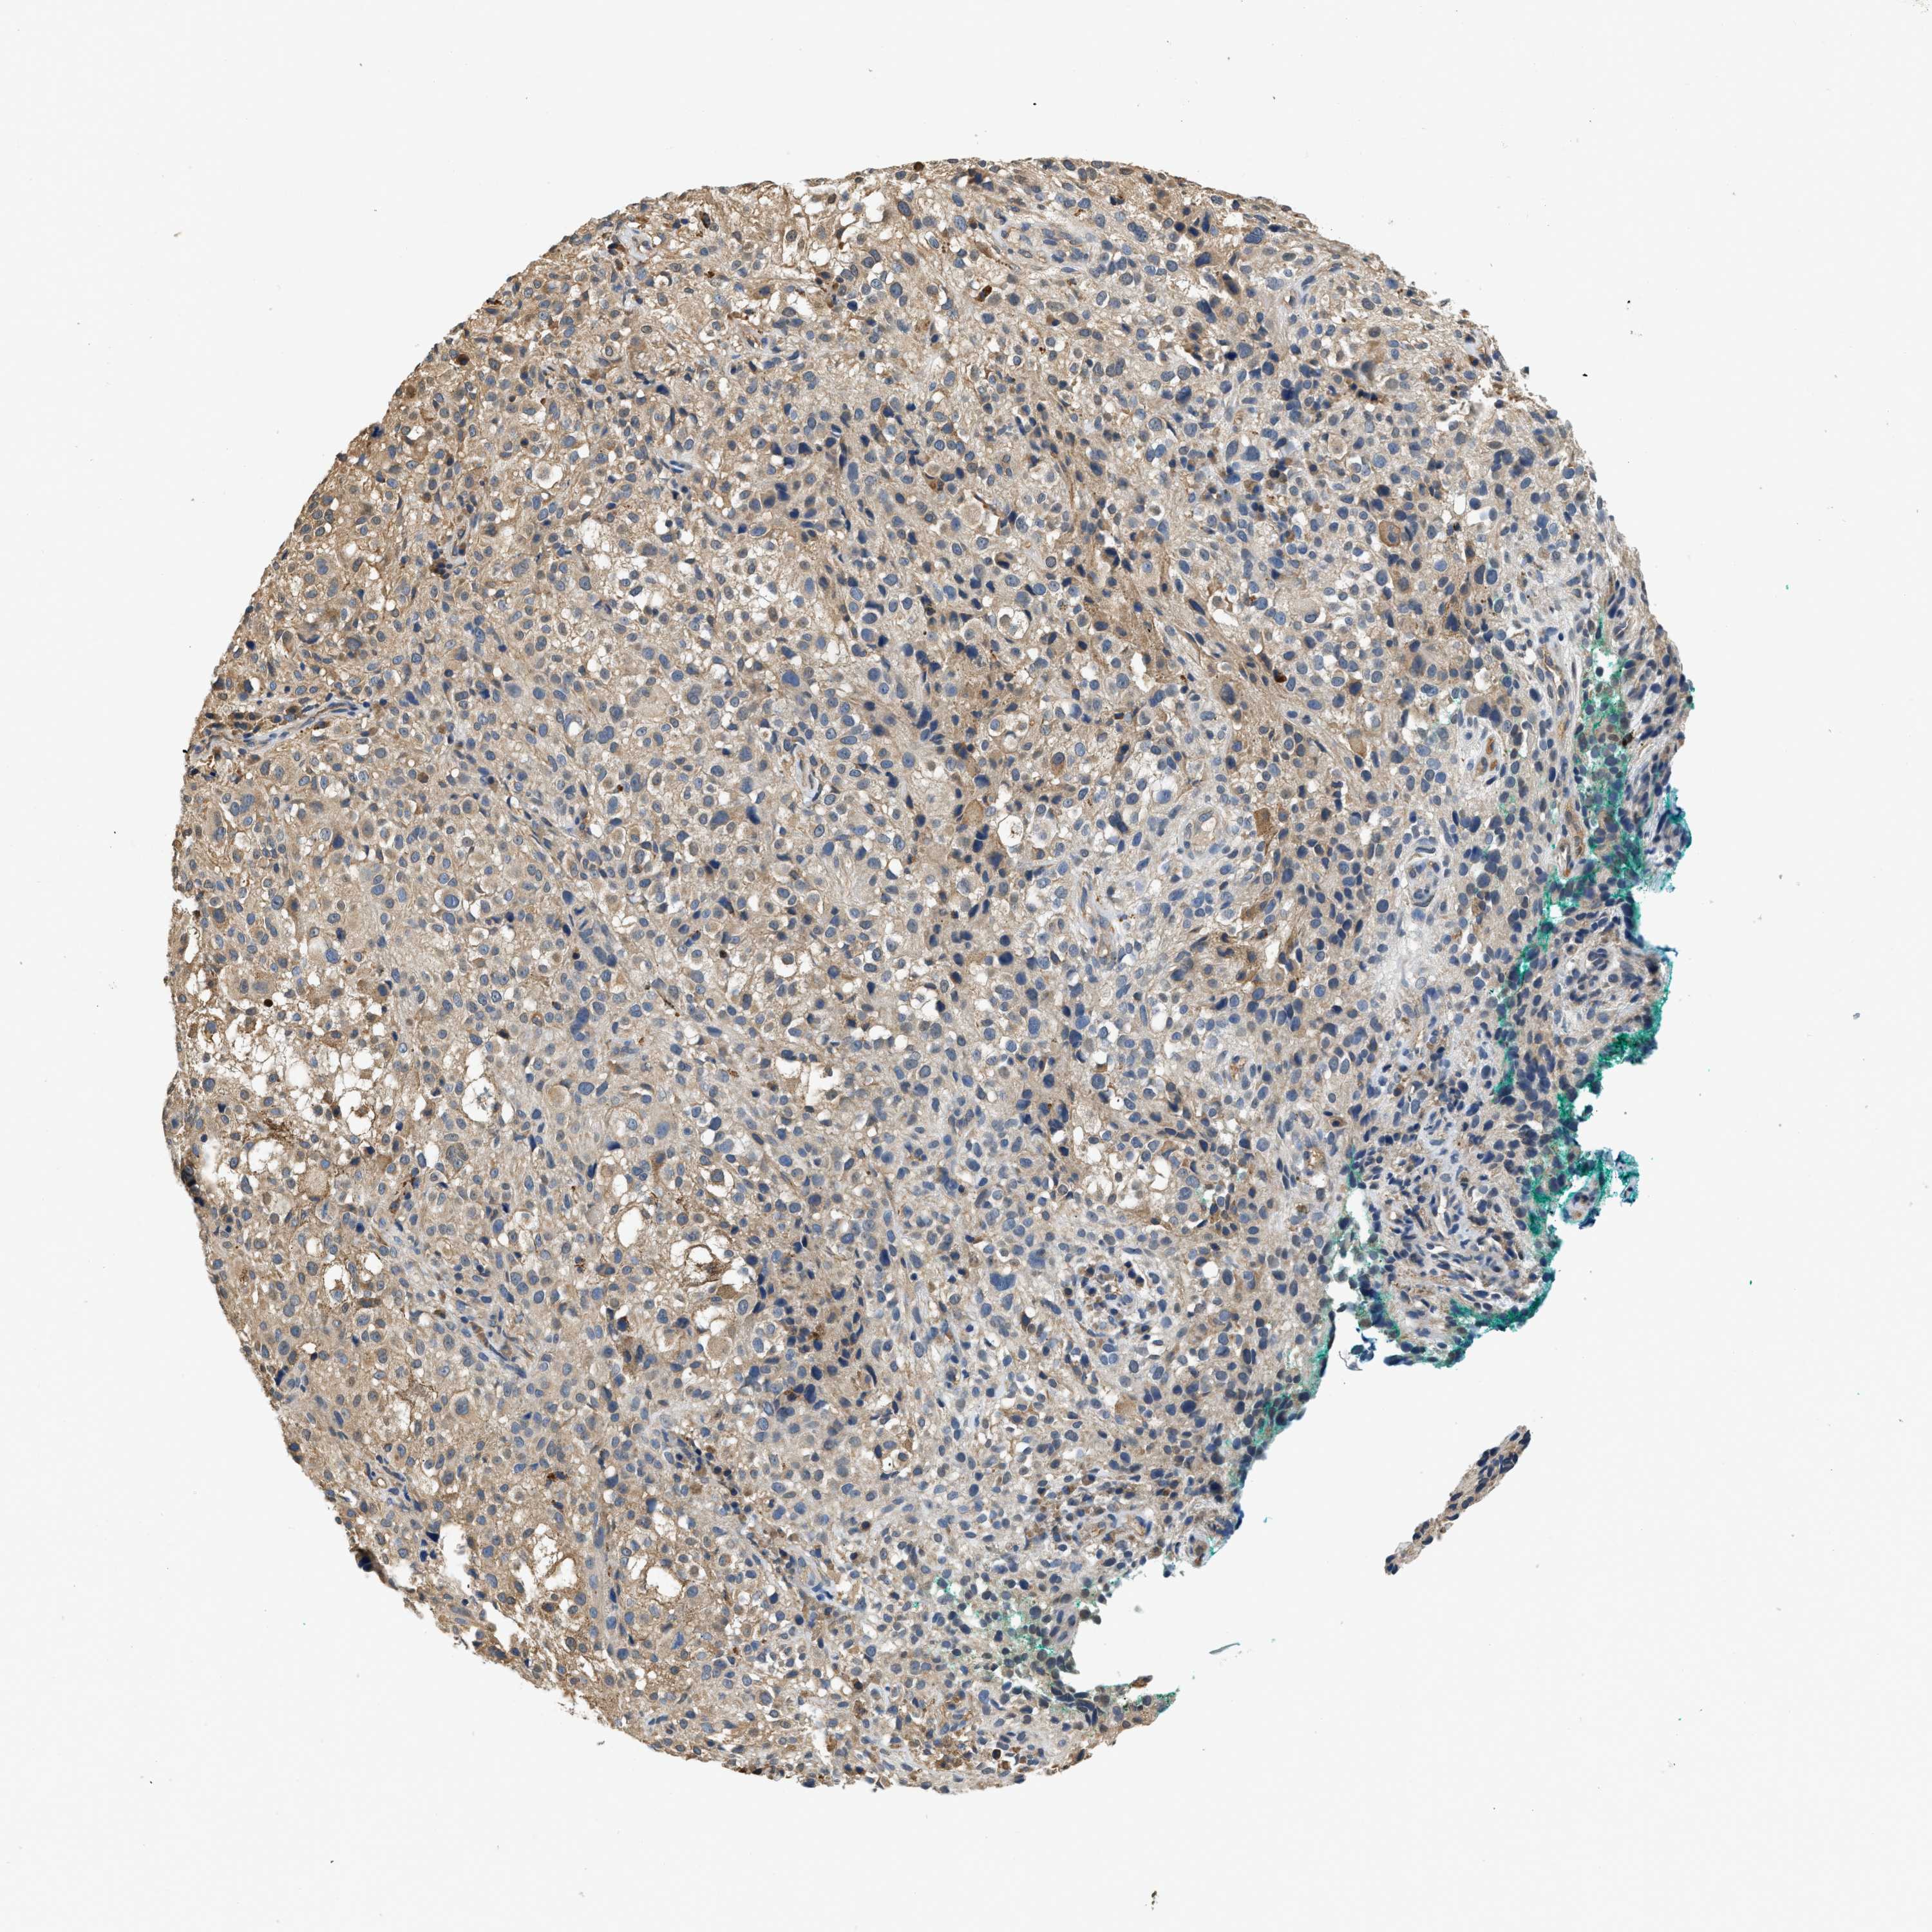

MELANOMA - Protein expressioni

A mouse-over function shows sample information and annotation data. Click on an image to view it in a full screen mode. Samples can be filtered based on level of antibody staining by selecting one or several of the following categories: high, medium, low and not detected. The assay and annotation is described here.

Note that samples used for immunohistochemistry by the Human Protein Atlas do not correspond to samples in the TCGA dataset.

Antibody stainingi

Antibody staining in the annotated cell types in the current human tissue is reported as not detected, low, medium, or high, based on conventional immunohistochemistry profiling in selected tissues. This score is based on the combination of the staining intensity and fraction of stained cells.

Each image is clickable and will lead to virtual microscopy that enables deeper exploration of all samples and also displays staining intensity scores, fraction scores and subcellular localization as well as patient and tissue information for each sample.

Antibody HPA018676

Staining

High

Medium

Low

Not detected

Intensity

Strong

Moderate

Weak

Negative

Quantity

>75%

75%-25%

<25%

None

Location

Nuclear

Cytoplasmic/membranous

Cytoplasmic/membranous,nuclear

Malignant melanoma, NOS

Malignant melanoma, Metastatic site